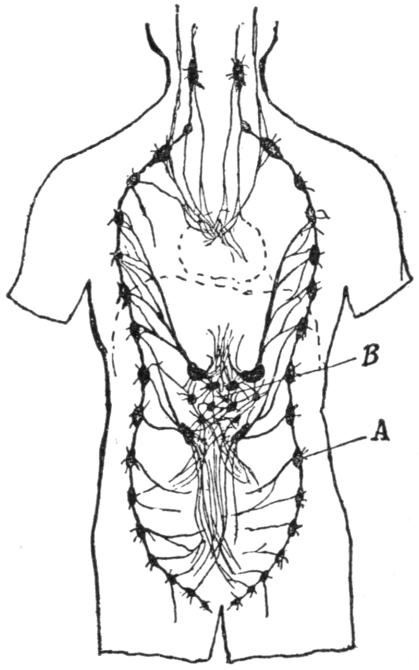

| VIII. | The Nervous System | H 117 |